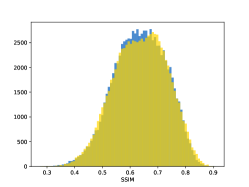

To visualise similarity metrics that compare image pairs (RMSE, SRE, SSIM) two metric distributions are generated: intra-similarity and inter-similarity. For each compared sample 300 random images are selected. The inter-similarity distribution is calculated for each image pair combination from both compared samples e.g. generated images of COVID-19 and real images of COVID-19. For the intra-similarity, all pairs of images in a single sample e.g real images of COVID-19 are considered. By comparing the shape of intra-similarity for the training subsample (Dataset) with the inter-similarity of training and generated samples the quality of the generated sample can be judged. It is also possible to compare in this way between the four image classes present in the dataset. The resulting distributions of inter-similarity of COVID-19 and the three remaining classes are compared in Fig. 4 to distributions of intra-similarity of the COVID-19 sample for each metric. All metrics, as expected based on available medical evidence Rubin et al. (2020), indicate that there are visible differences not only between COVID-19 and normal samples but also between viral pneumonia and lung opacity. Therefore, all classes should be distinguishable.

To visualise differences between synthetic and real samples distributions are generated for each of the RMSE, SRE and SSIM metrics: intra-similarity and inter-similarity. For each compared sample 300 random images are selected. The inter-similarity distribution is calculated for each image pair combination from both compared samples e.g. generated images of COVID-19 and real images of COVID-19. For the intra-similarity, all pairs of images in a single sample e.g real images of COVID-19 are considered. The distributions for generated samples describe very well the distributions for corresponding real images as shown in Fig. 6.

The quality of generated images is also confirmed with classical similarity metrics. The distributions of those similarity measures between generated and real images are compared for each sample with the distribution obtained within the real samples 6. The distributions for generated samples describe very well the distributions for corresponding real images. For an example see the results for the SSIM metric presented in Fig. 10. The small visible differences are almost insignificant compared to differences observed between the classes in Fig. 4.